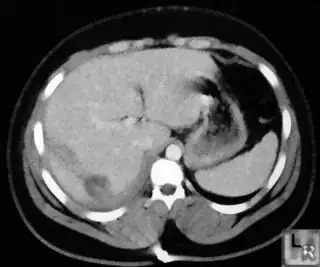

Below I apply two successive morphological openings to the image using a 3x3 circular kernel, and then apply k-means clustering to the gray levels. From your sample images and some I found on the internet, I decided to set k = 4. If you are using high-resolution images, first downsample them to dimensions ~400-600. Otherwise the morphological operation may not have a significant effect, and the k-means will be slow.

Below are some of the opened and segmented images. Of course there's more to be done in terms of

- separating out the liver region

- generalizing this to a large dataset

but hope this is at least a starting point.

You might be able to narrow down the region or interest by filtering out the darkest and the lightest regions from the segmented image. For this, use the k-means cluster centers, check for the extreme values (max and min) and remove the corresponding k values from the labeled image. Then you can look for large structures to the left of the result image. Worst case, you might get a hole on the left side when the extreme region filtering goes wrong. I've updated the code and results.